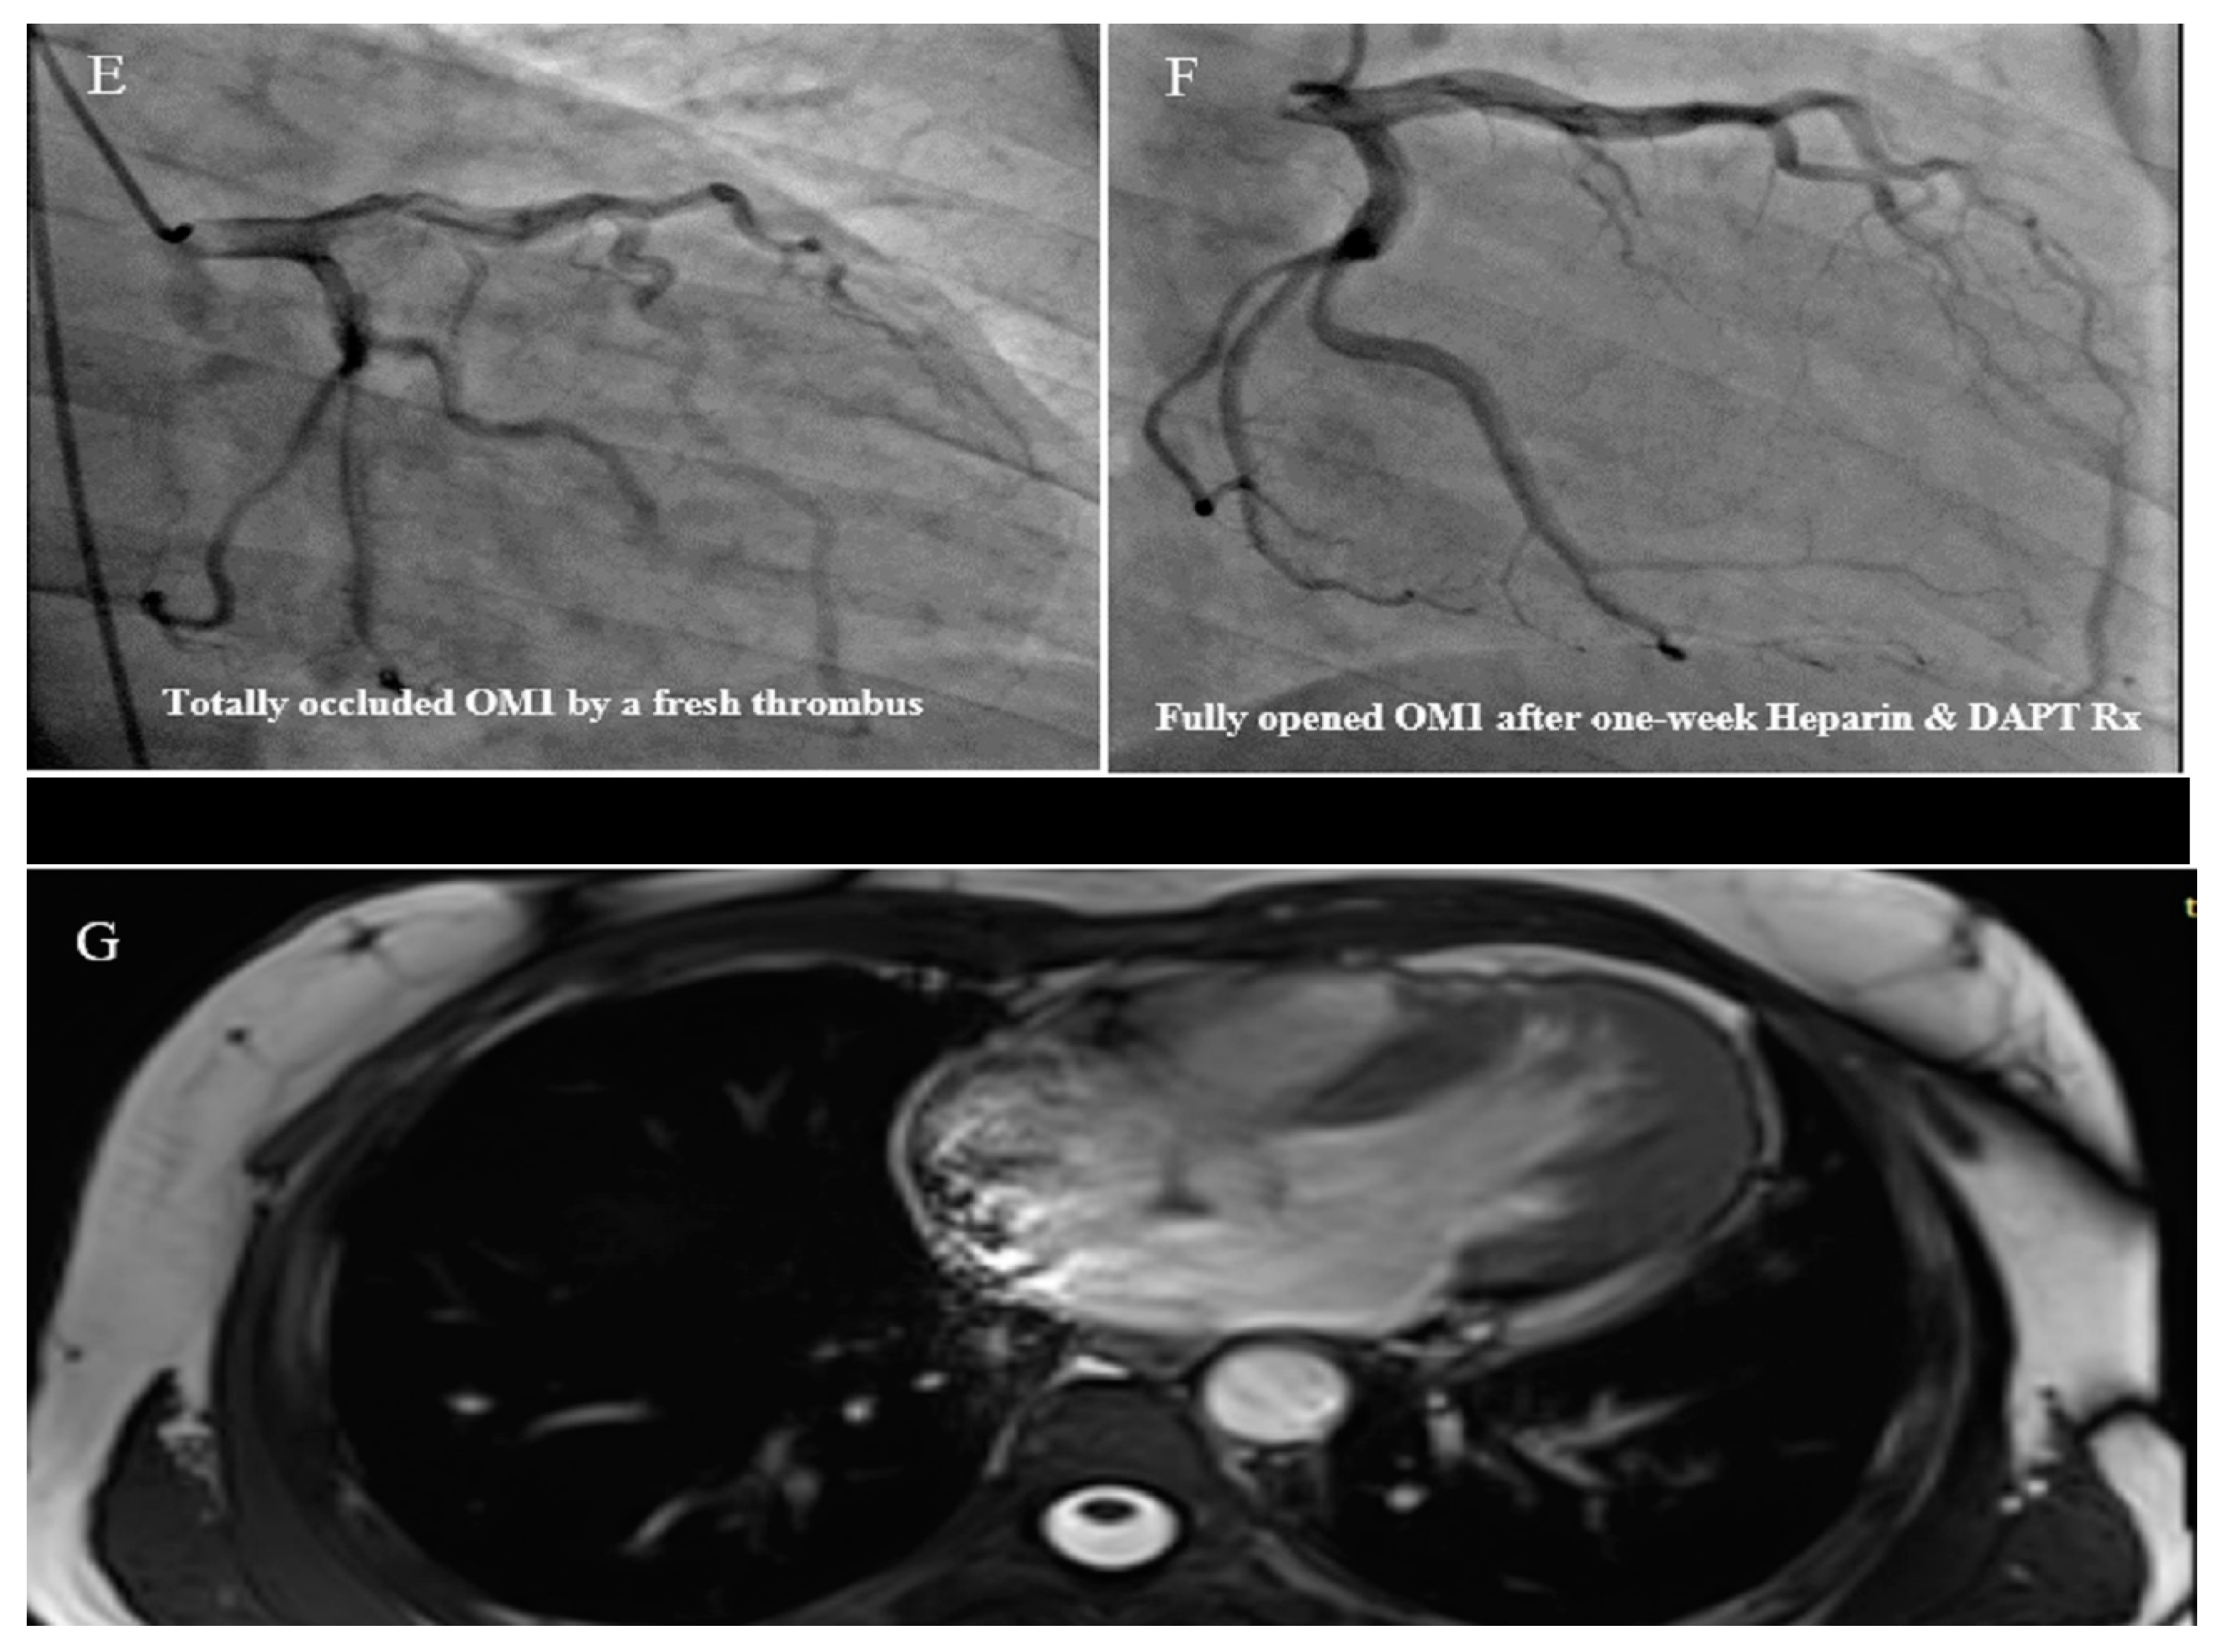

2.3. Case #3. NCLV with Aortic Dilation Complicated by Coronary Embolism

| 3 | M | 37 | Acute retrosternal pain with radiation to both shoulders since three hours prior to admission | − | NCLV, LVEF = 55% | Aortic dilation and coronary embolism | + | + | Anticoagulation plus dual antiplatelet therapy for two weeks switched to lifelong warfarin | Doing well |